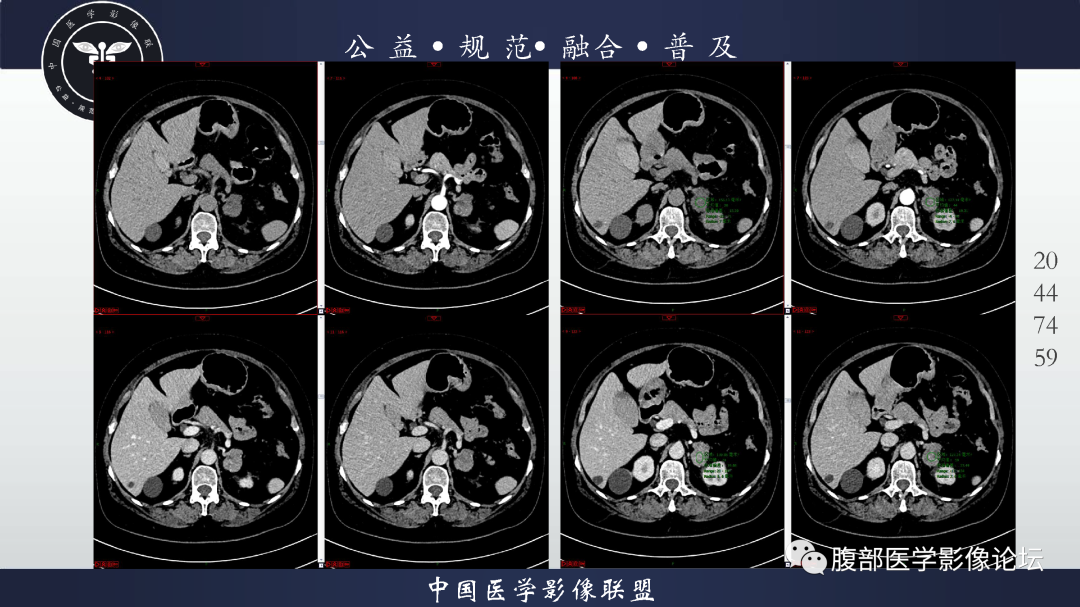

【病例】肾脏透明细胞癌1例CT影像-2